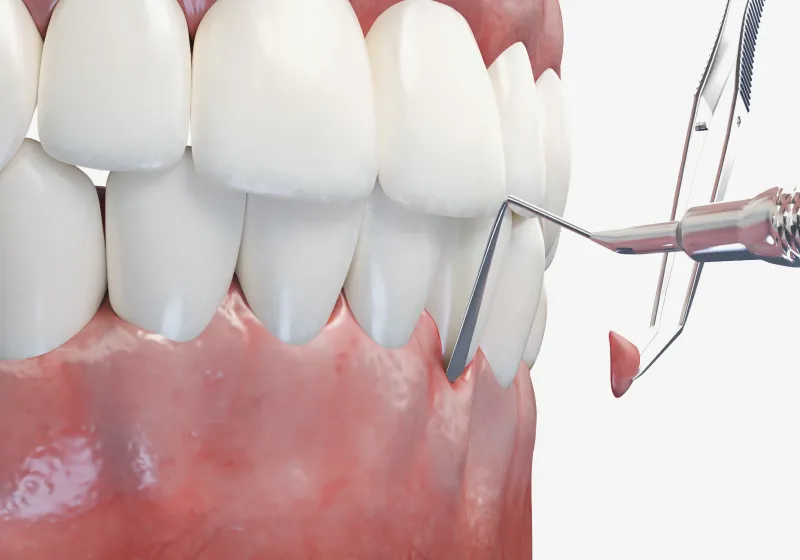

軽度の歯肉炎や初期の歯周炎であれば、まずは原因であるプラーク(歯垢)や歯石を取り除く「スケーリング」と、歯根の表面を滑らかに整える「SRP(ルートプレーニング)」が中心です。

専用の器具を使って歯ぐきの奥まで清掃し、細菌が再び付着しにくい状態に整えます。 -

中等度以上の歯肉炎

しかし、炎症が中等度以上に進行している場合には、歯ぐきの奥深くまで歯石や感染組織が入り込み、通常のクリーニングだけでは改善が難しくなります。

その場合は「歯周外科治療」を行い、歯ぐきを一部開いて直接歯根を露出させ、炎症の原因をしっかりと除去します。

これにより、深くなった歯周ポケットをリセットし、再感染を防ぐことができます。 -

フラップ手術

(歯肉剥離掻爬術)また、炎症が歯ぐきの深部まで進行している場合は、「フラップ手術(歯肉剥離掻爬術)」を実施します。

歯ぐきを丁寧に開いて奥深くの歯石や感染組織を直接確認しながら取り除く方法で、マイクロスコープを併用することで精密かつ低侵襲な処置が可能です。

これにより、術後の腫れや痛みを抑え、治癒を早める効果も期待できます。 -